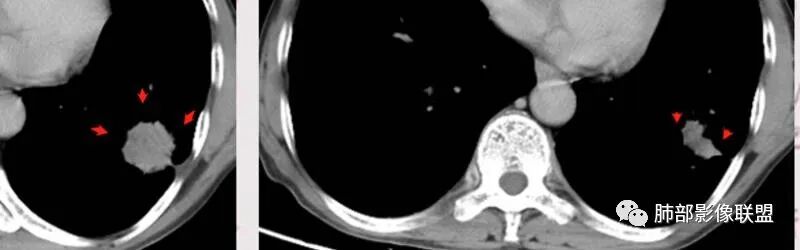

临床病史很长,背痛9年可能与左侧胸膜炎有关。两上肺陈旧性结核伴肺气肿没有问题。左下肺病灶,分叶毛刺、胸膜凹陷、指状凸起,增强轻度强化,腺癌问题不大。右侧附加题有些困难,病灶内血管显影,不像结核的表现,先把结核否掉?鳞癌和慢性脓肿的鉴别:支持良性的征像,低密度区内也有细小血管影,不像鳞癌坏死?与胸膜关系整体还是比较和谐,边缘还算光整,毛刺都在远端,不支持慢性脓肿的的地方,周围支气管管壁都很干净。恶性征像,与支气管的关系图片给的不够。坏死边缘不光整,有些浅分叶。总体,我觉得坏死区血管的存在更有价值,验证一下,右侧首先考虑慢性脓肿。

右肺增强有强化,湖泊样坏死

4.右侧坏死明显,内部囊变坏死边缘部分清楚、部分不清

今天晨读我觉得最有特征性的就是那个强化,环状强化,周围强化比较明显的是癌,血供丰富,中间应该是肉瘤粘液变性,而且边界比较清楚,这个也算肉瘤样癌比较有特征性的,其他的跟其他恶性确实不好鉴别

主要征象:病灶分叶不明显、较光整,局部胸膜栽赃,支气管门口堵塞,有推移迹象;增强后坏死明显,内部囊变坏死边缘部分清楚、部分不清楚,病灶内可见血管,局部稍毛糙,实性部分强化较明显,总体考虑恶性病变。一部分征象指向鳞癌(支气管截断、坏死较多,病灶内血管破坏),但又有肉瘤的一些特点(病灶较大,缺乏分叶,坏死边界清晰),要考虑到肉瘤样癌。

3、本病好发于60岁以上的老年男性,多数有吸烟史。周围型多于中央型,病灶边缘较清楚,多数光整圆钝,部分可见浅分叶,少数有毛刺,无胸膜凹陷征出现。CT平扫时呈软组织密度,较小的肿块密度较均匀,肿块较大时中央常出现坏死。增强扫描肿块多呈斑片状不均匀强化,而肿瘤周边厚薄不均的囊壁样强化较具特征性。周围型多数位于胸膜下,常常侵犯胸膜或胸壁。